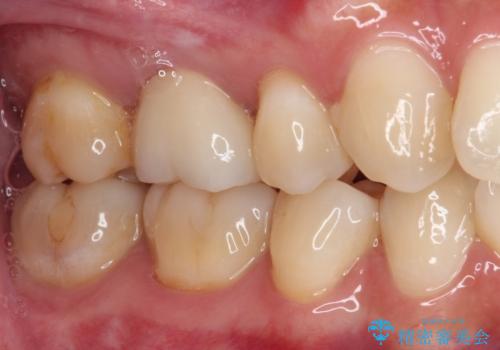

セラミッククラウンを装着する前に仮歯を装着しましたが、その時点で強い痛みはほぼ改善され、セラミッククラウン装着後には痛みはもちろん、しみる症状も感じることがなくなりました。